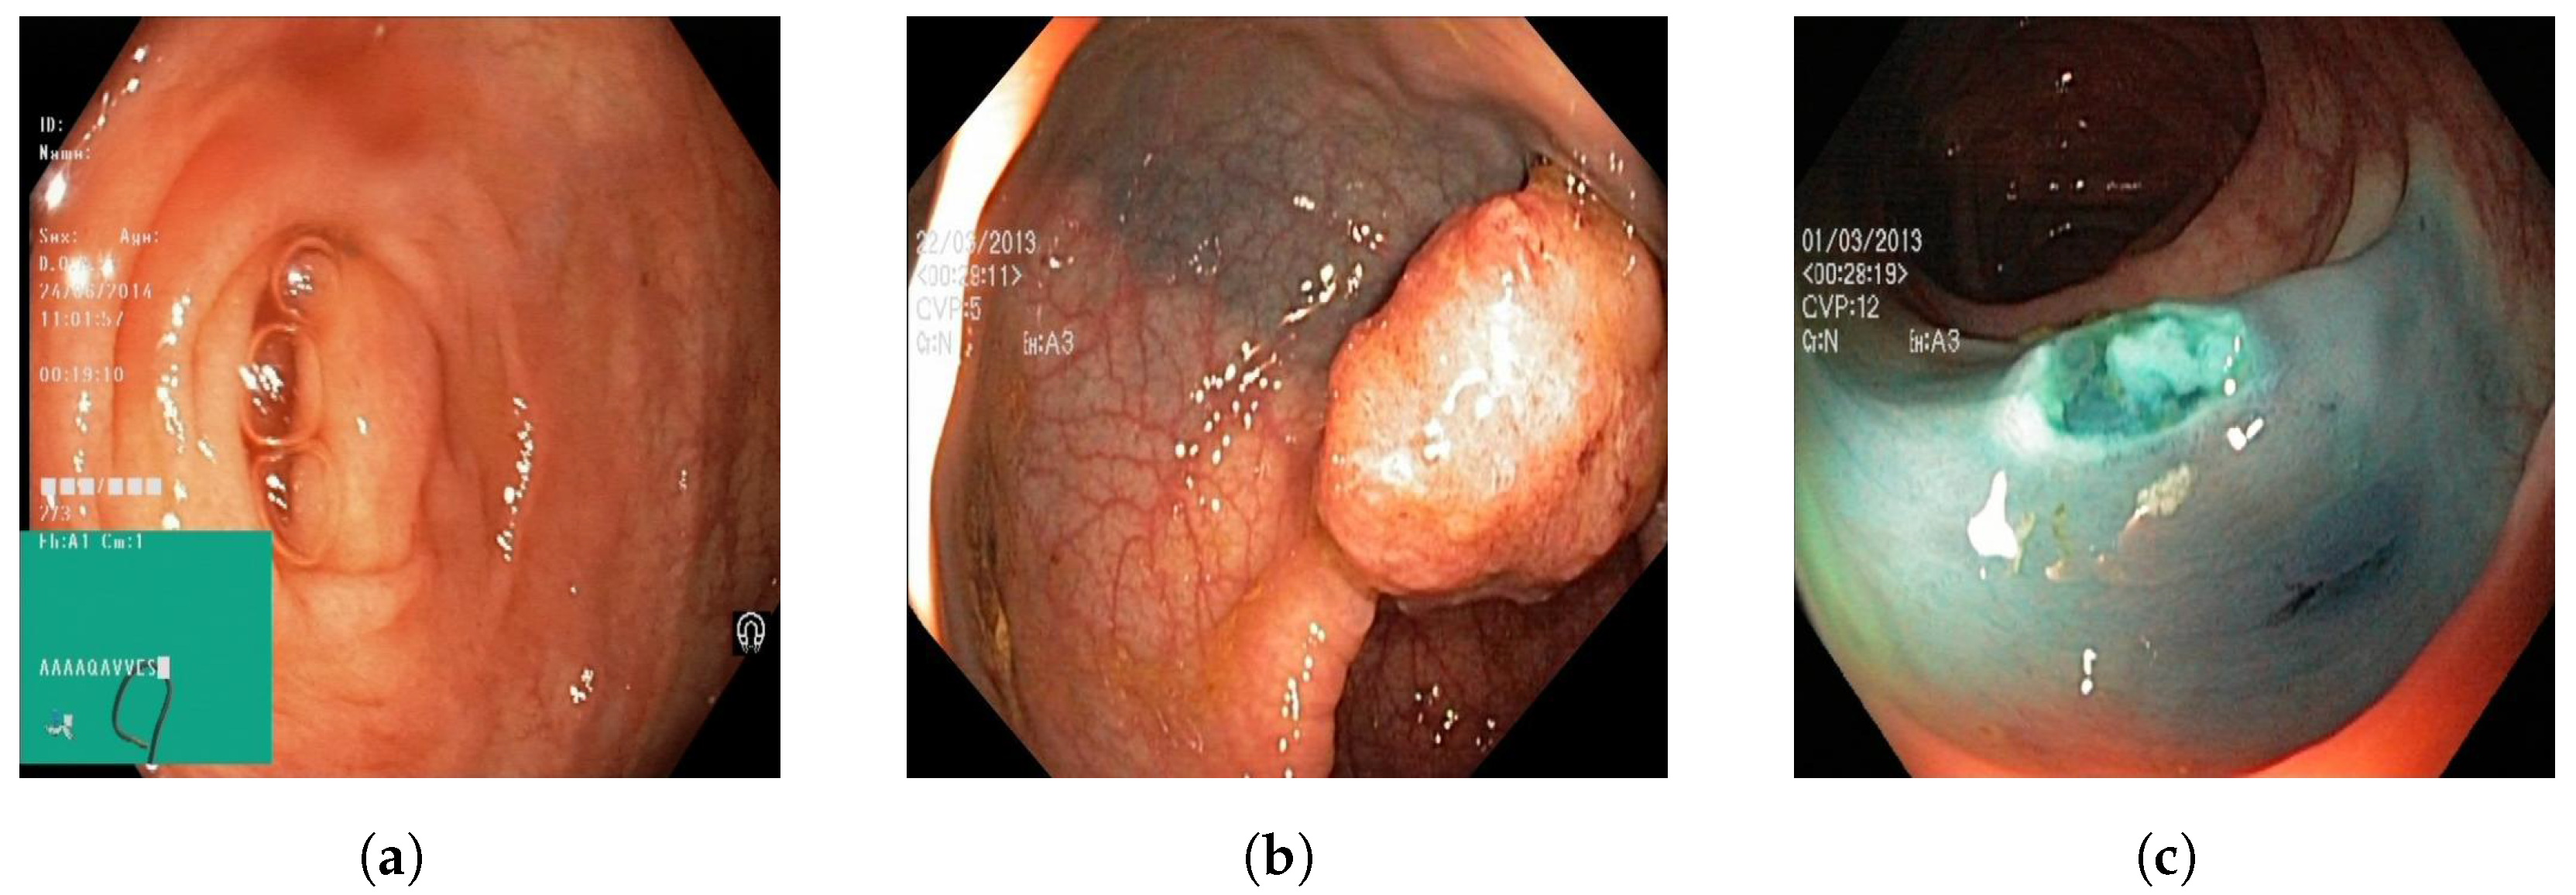

An open-source online gastrointestinal endoscopy database was used to train the machine learning models. The database used in this research is titled “HyperKvasir”, curated by Borgli et al. and sourced from Simula Datasets [22]. The dataset consists of 110,079 images of the GI tract, out of which 10,662 are labeled and 99,417 are unlabeled images. The labeled image dataset consisted of anatomic landmarks such as the cecum, ileum, and retroflex-rectum. The dataset also has pathologic findings, such as polyps, as well as therapeutic interventions, such as dyed-resection margins. Sample images from all three classes are outlined in Figure 1. The complete data set, containing all the images utilized for the three machine learning models, can be accessed via [23].

A total of 601 images were used to train the image classification models to train the models on differentiating between normal colonic tissue, polyp, and resected polyp. Further, 201 images of the cecum were used as “normal colonic tissue”. The model was trained using a dataset consisting of 200 images of polyps found in various sections of the lower gastrointestinal tract, along with an additional set of 200 images depicting dyed-resected polyp margins. The purpose of this training was to differentiate between polyps that were still intact and those that had been surgically removed. All the images were cropped to ensure a 1:1 aspect ratio (~640 × 640 pixels). All the images were also ensured to be the same format of Joint Photographic Experts Group (JPEG). Images that at least two authors deemed to be subjectively obstructed or suffering from over/underexposure were subsequently excluded from the HyperKvasir dataset, resulting in the final selection of 601 images. Three different image classification models were trained: GTM, RF3, and YOLOv8n.

Figure 1. Sample images of (a) normal colonic tissue, (b) pylop, and (c) resected pylop.

Comparing all three models, GTM demonstrated exceptional performance in the classification task, achieving perfect precision, recall, and F1 scores for all classes on both the original test set and the external validation set. GTM’s key advantages include its ease of use and accessibility, making it an excellent option for researchers or practitioners without extensive machine learning expertise. GTM is a classification model, not a detection model; therefore, its architacture is simpler than the RF3 and YOLOv8n models, which are detection models. The high accuracy, precision, recall, and F1-score of the GTM model could be explained by the fact that it classifies the different images into “normal”, “polyp”, or “resected”. However, RF3 and YOLOv8n detect the location of the polyp in the image itself. In addition, all of the “resected polyp” images from the HyperKvasir dataset [22] were dyed blue; therefore, the GTM model could theoretically use the color data to classify the resected polyps correctly. GTM was still able to correctly classify between the “normal” and “polyp” classes even though they had similar-looking backgrounds. Many gastroenterologists dye polyps blue before polyp resection for better visualization; therefore, this is clinically relevant. RF3 performed well, with competitive metrics on both the original test set and the external validation set. One of the significant advantages of RF3 is its ability to handle more complex tasks thanks to its capability for bounding box regression and object detection using deformable convolution layers. YOLOv8n also displayed competitive performance, with metrics falling between those of GTM and RF3. The better performance shown by the YOLOv8n model as compared to the RF3 model could be indicated by the fact that this was the only model with augmentation steps added, thus possibly biasing the results for this model.